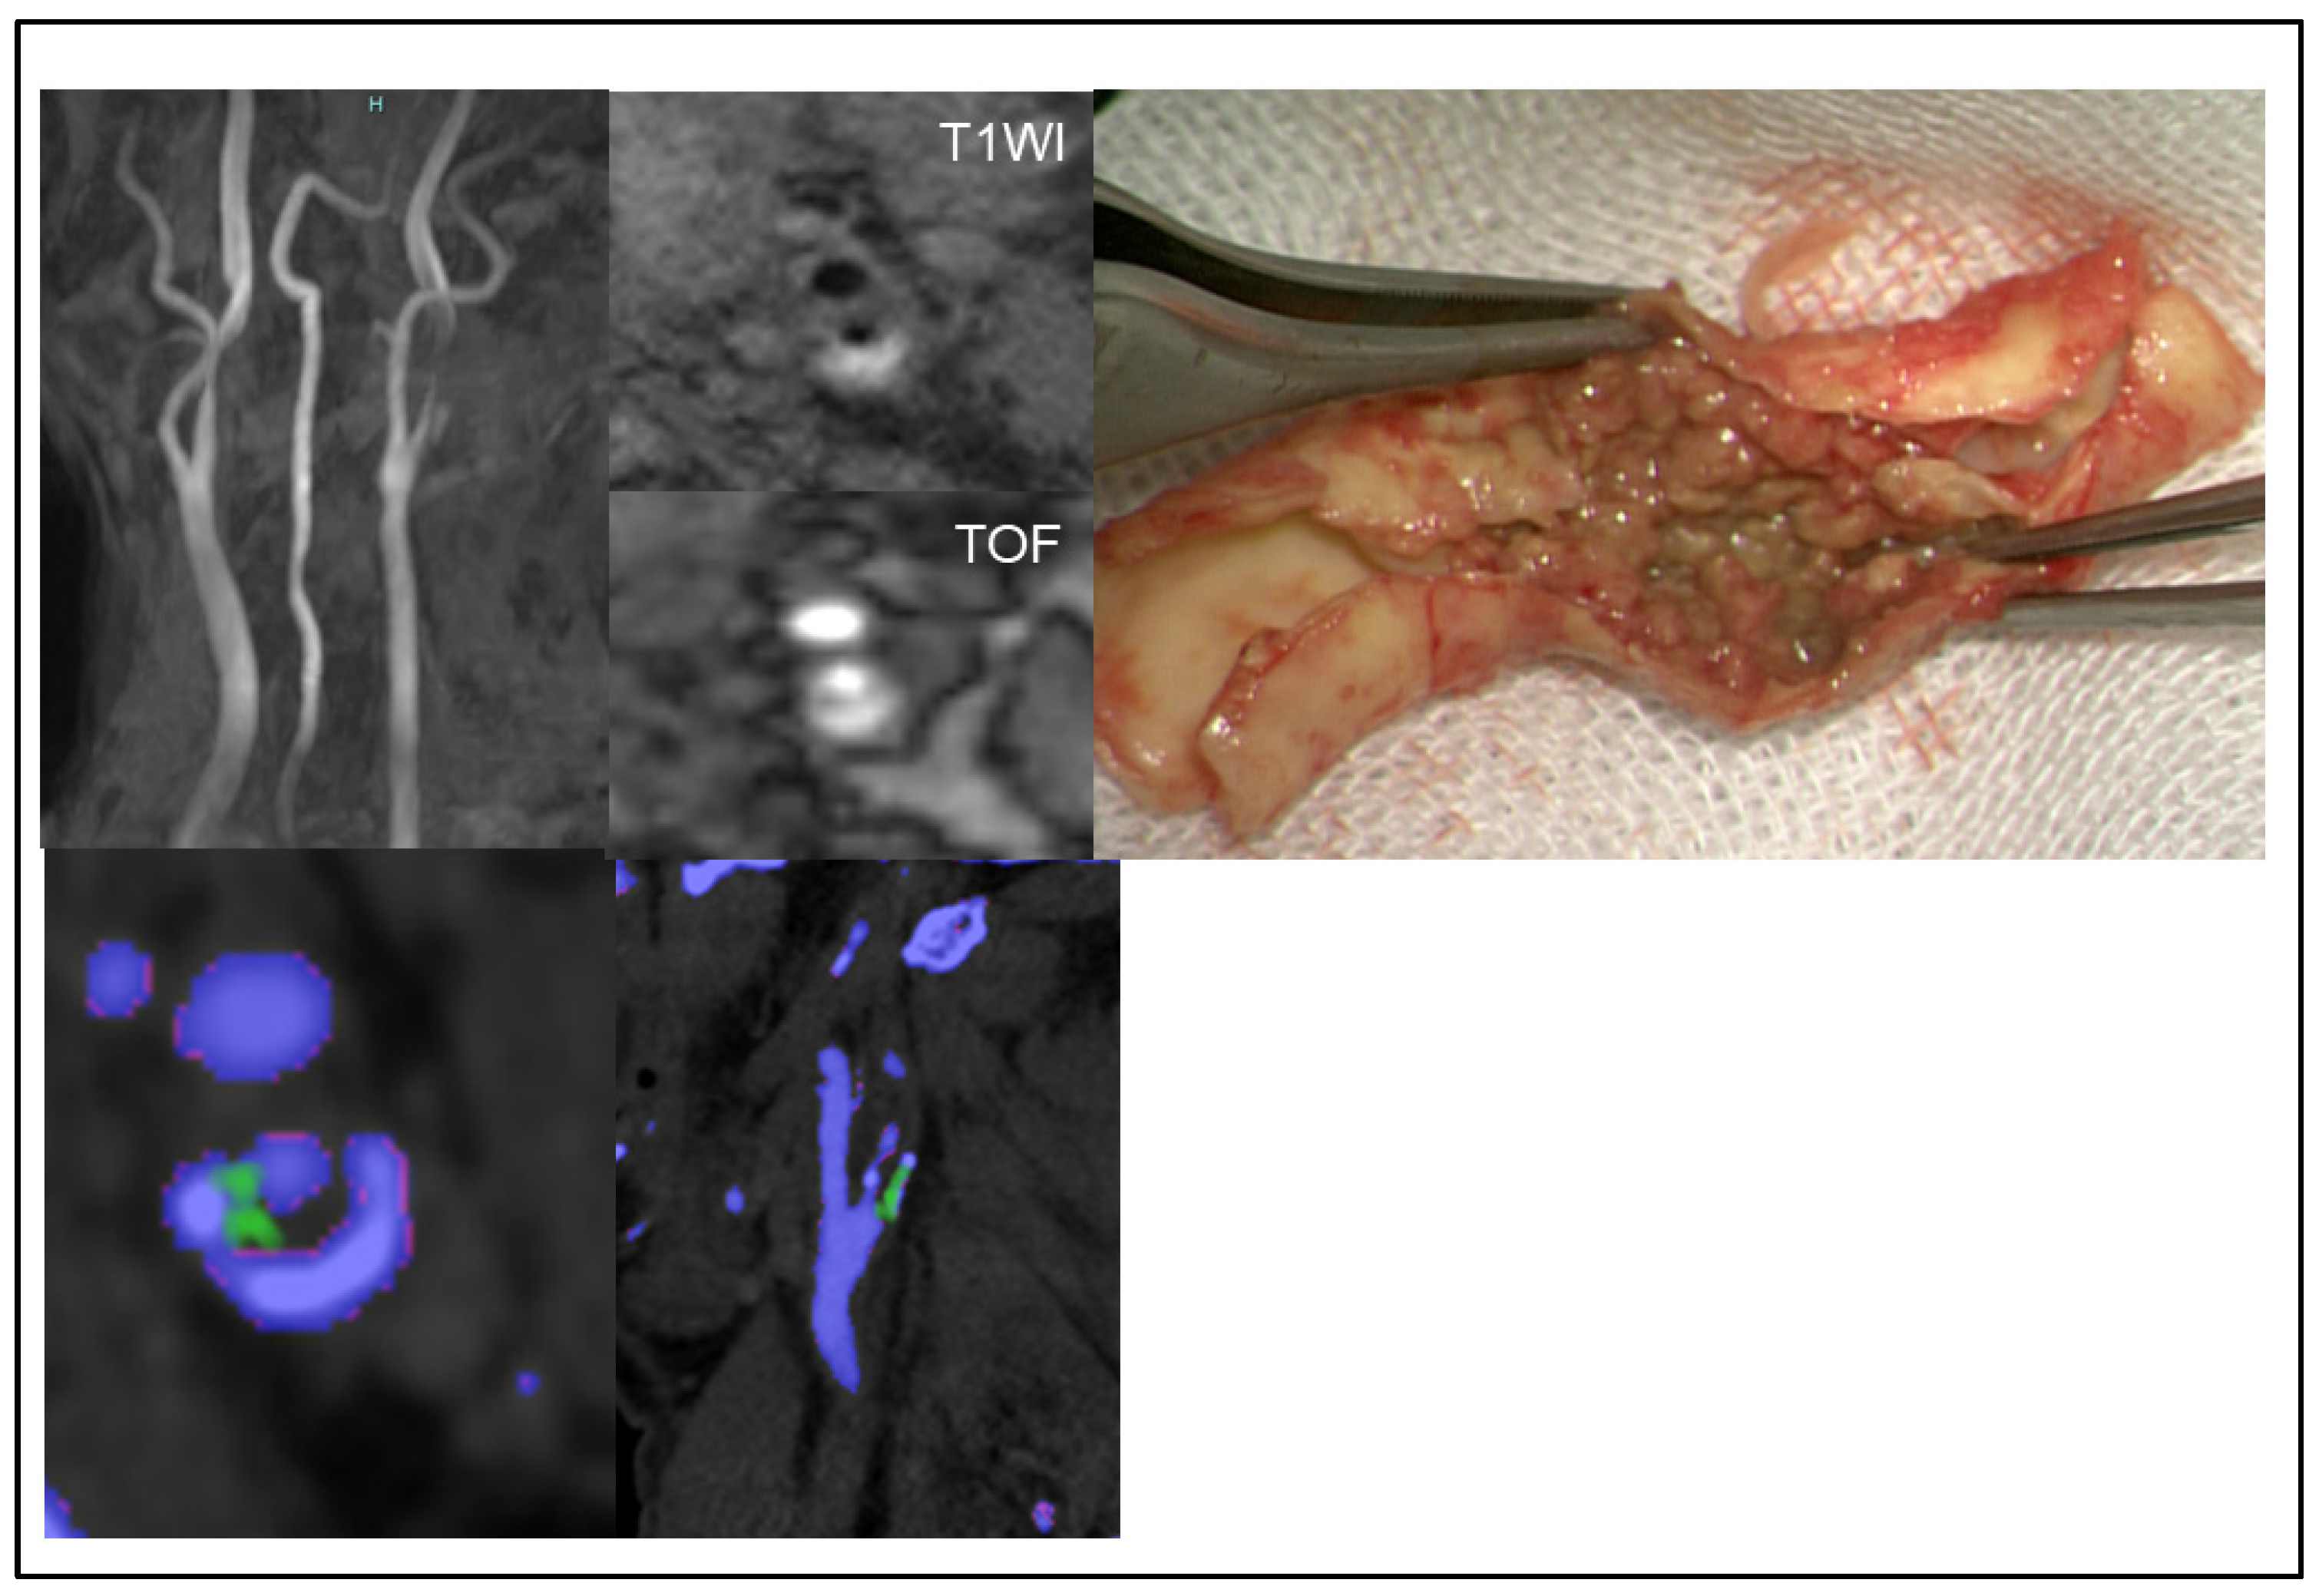

2.4. Assessing MSU Deposits in Plaque and Stenosis Degree Using DECT

2.5. Assessing Plaque Composition Using MR Imaging

3.4. MSU Deposits Detected Using DECT and Its Accuracy